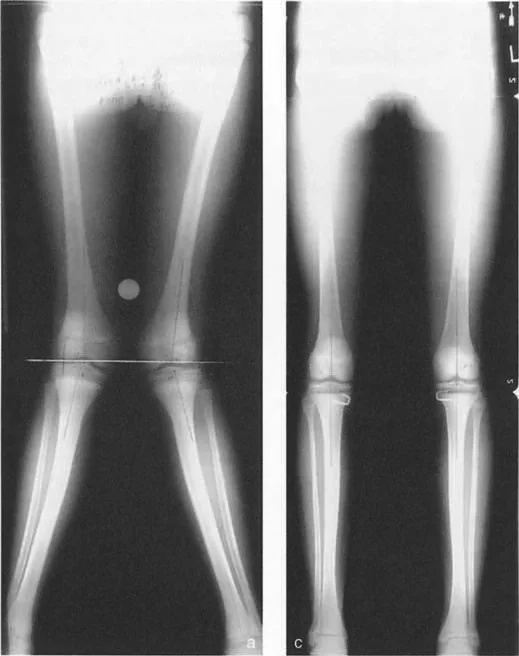

القياسات الشعاعية الدقيقة

تعتبر الأشعة السينية (Orthoroentgenograms) هي الأداة الأساسية لقياس أطوال العظام بدقة. يتم أخذ صور شعاعية للطرفين السفليين معًا لتقييم طول الفخذ والساق بشكل فردي. هذه القياسات ضرورية لتحديد مقدار التفاوت الحالي.

تُستخدم هذه البيانات، مثل بيانات أندرسون (Anderson data)، لإنشاء جداول مرجعية لأطوال العظام الطبيعية حسب العمر والجنس، والتي تُعد أساسًا لطرق التنبؤ بالنمو.